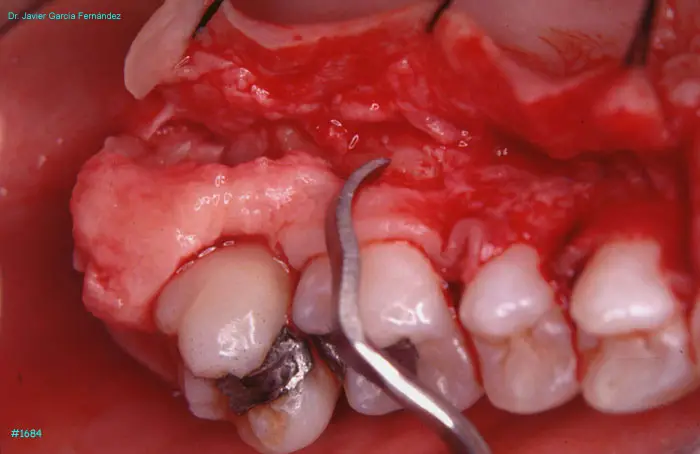

Atlas of Surgical Techniques in Periodontics. Chapter IV. Atlas de Técnicas Quirúrgica en Periodoncia

image 196